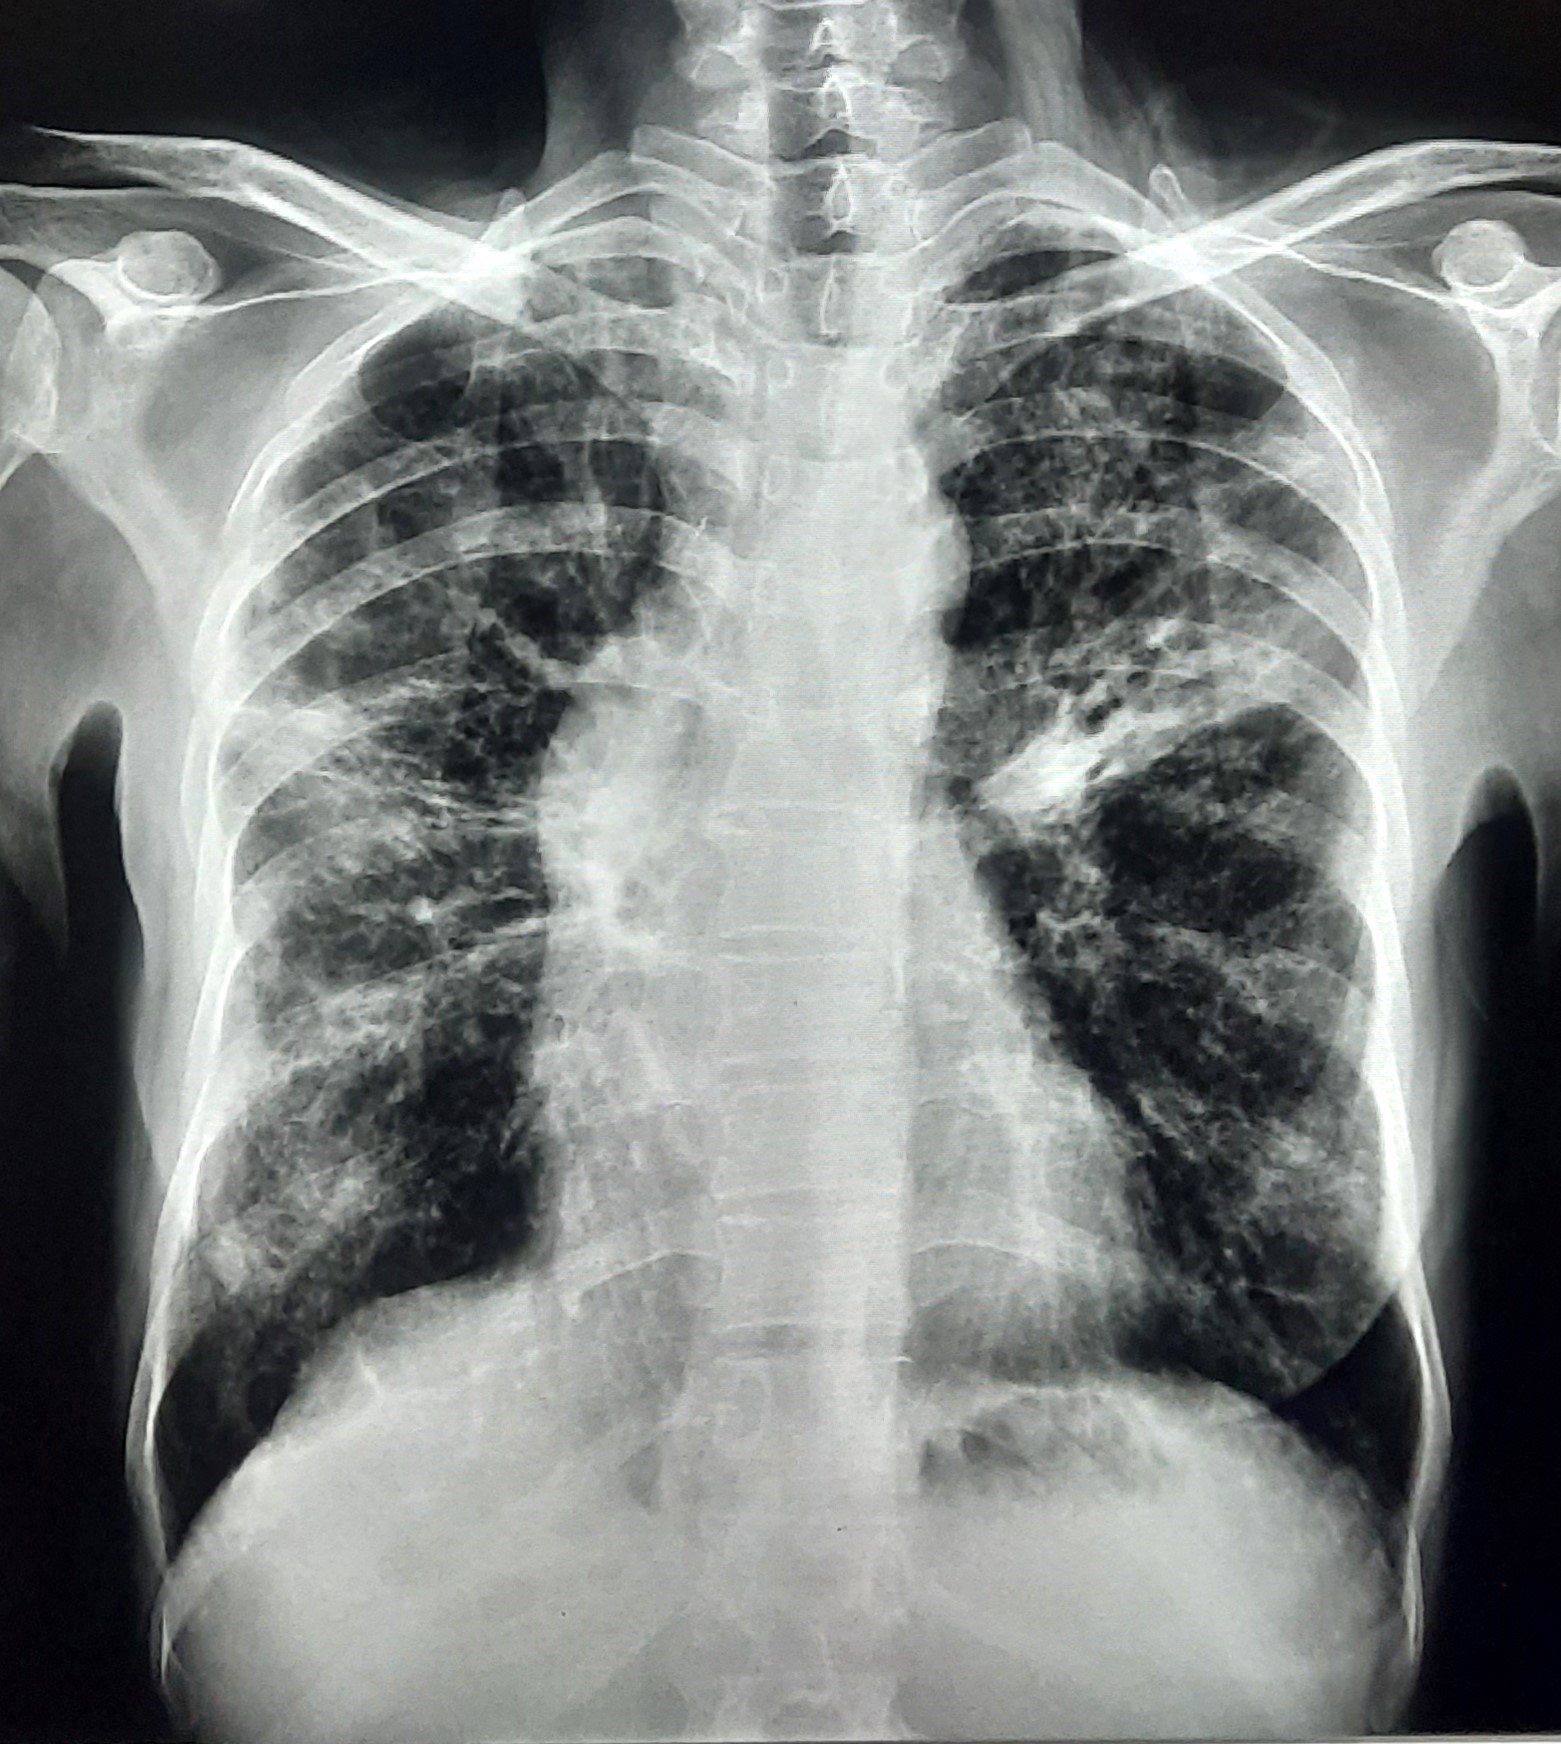

| 152 | IGGMC, Nagpur, Nagpur | P2 | 29-4320 | Dewakabai Thakare | Consent taken on Paper | 80 Yrs. |

Provisional Diag : Post TB Sequel

Final Diag : Post TB sequelae with emphysematous Hyperlucency |

Post TB Sequelae | Left Lower Zone Ill Defined Opacities Present With Hyperlucency Left Lower Zone | Abnormality visible on x-ray |